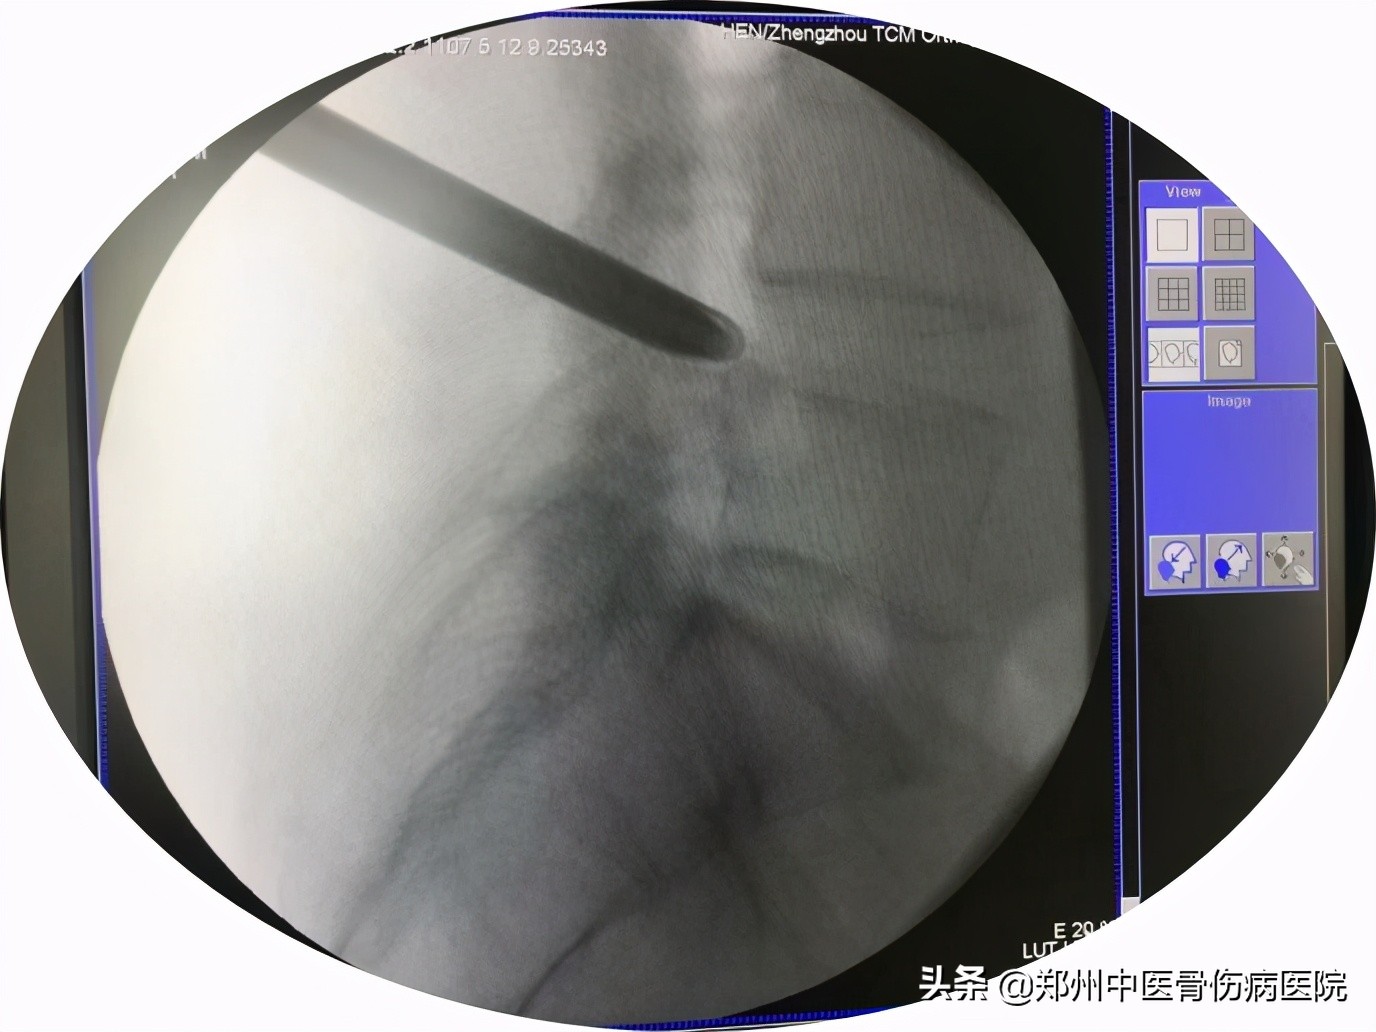

半个月前双腿也开始疼痛,尤其是左臀部疼痛麻木,不能久站久坐,贴膏药也没有改善,听亲戚介绍她来到了郑州中医骨伤病医院,经过检查发现,秦阿姨腰4-5节段腰椎间盘突出伴侧隐窝狭窄。

在结合病情与检查结果,给出了秦阿姨的治疗方案——进行经皮内镜椎间盘切除手术即俗称的 椎间孔镜手术。

近年来随着经皮椎间孔镜(PELD)技术在国内迅猛开展,这是一项开展成熟的微创脊柱外科内镜技术,也是一项充满崭新生命力的新技术。该技术是真正意义上的脊柱内窥镜系统,内窥镜直视下操作可清晰、完整摘除突出组织或脱垂髓核清除骨质增生、治疗椎管狭窄症、同时该套设备配备了360度射频刀头能够在术野内利用射频技术修补破损的纤维环;脊柱周围肌肉、韧带、骨性结构得到最大程度保护脊柱稳定性;创伤小、恢复快、安全性高。

培养椎间孔镜在安全工作三角区实施手术,在椎间盘纤维环之外做手术在内窥镜直视下可以清楚的看到突出的髓核、神经根、硬膜囊和增生的骨组织。然后使用各类抓钳摘除突出组织、镜下去除骨质、射频电极修复破损纤维环。手术创伤小:皮肤切口仅7mm,如同一个花生大小,出血不到20m,术后仅缝1针。

椎间孔镜通过在椎间孔安全三角区、椎间盘纤维环之外彻底清除突出或脱垂的髓核和增生的骨质来解除对神经根的压力,消除由于对神经压迫造成的疼痛。其手术方法是通过特殊设计的椎间孔镜和相应的配套脊柱微创手术器械、成像和图像处理系统等共同组成的一个脊柱微创手术系统。在彻底切除突出核的同时清除骨质增生、治疗椎管狭窄症、可以使用射频技术修补破损的纤维环等。